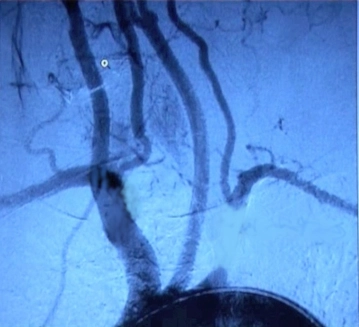

Angiografia por Subtração Digital (DSA), Angiografia por RM